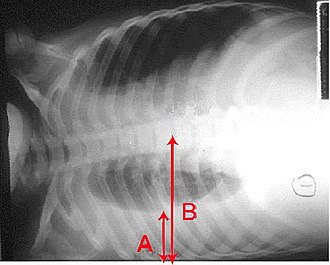

U svrhu postavljanja dijagnoze često se koristi rentgen prsišta.<ref name=Develop11/> Slikovne su pretrage potrebne u osoba s blagom bolešću ako se očekuju moguće komplikacije, u bolesnika čije se stanje ne popravlja usprkos liječenju i u bolesnika u kojih ne postoji sigurnost o uzroku bolesti.<ref name=Develop11/><ref name=BTS09>{{cite journal|last=Lim|first=WS|coauthors=Baudouin, SV, George, RC, Hill, AT, Jamieson, C, Le Jeune, I, Macfarlane, JT, Read, RC, Roberts, HJ, Levy, ML, Wani, M, Woodhead, MA, Pneumonia Guidelines Committee of the BTS Standards of Care, Committee|title=BTS guidelines for the management of community acquired pneumonia in adults: update 2009|journal=Thorax|date=rujan 2009. |volume=svezak 64 |issue=dodatak 3|pages=str. iii1.–55.|pmid=19783532|doi=10.1136/thx.2009.121434}}</ref> Ako je stanje bolesnika tako loše da je potrebna hospitalizacija, preporučuje se učiniti rentgen prsišta.<ref name=BTS09/> Nalazi rentgenske pretrage ne odražavaju uvijek težinu bolesti, i na temelju njih se ne može pouzdano razlučiti bakterijska od virusne infekcije.<ref name=Develop11/> | U svrhu postavljanja dijagnoze često se koristi rentgen prsišta.<ref name=Develop11/> Slikovne su pretrage potrebne u osoba s blagom bolešću ako se očekuju moguće komplikacije, u bolesnika čije se stanje ne popravlja usprkos liječenju i u bolesnika u kojih ne postoji sigurnost o uzroku bolesti.<ref name=Develop11/><ref name=BTS09>{{cite journal|last=Lim|first=WS|coauthors=Baudouin, SV, George, RC, Hill, AT, Jamieson, C, Le Jeune, I, Macfarlane, JT, Read, RC, Roberts, HJ, Levy, ML, Wani, M, Woodhead, MA, Pneumonia Guidelines Committee of the BTS Standards of Care, Committee|title=BTS guidelines for the management of community acquired pneumonia in adults: update 2009|journal=Thorax|date=rujan 2009. |volume=svezak 64 |issue=dodatak 3|pages=str. iii1.–55.|pmid=19783532|doi=10.1136/thx.2009.121434}}</ref> Ako je stanje bolesnika tako loše da je potrebna hospitalizacija, preporučuje se učiniti rentgen prsišta.<ref name=BTS09/> Nalazi rentgenske pretrage ne odražavaju uvijek težinu bolesti, i na temelju njih se ne može pouzdano razlučiti bakterijska od virusne infekcije.<ref name=Develop11/> | ||

Rentgenska slika pneumonije se može podijeliti u [[lobarna pneumonija|lobarnu pneumoniju]], [[bronhopneumonija|bronhopneumoniju]] (koja se naziva i lobularnom pneumonijom) i [[intersticijska pneumonija|intersticijsku pneumoniju]].<ref>{{ | Rentgenska slika pneumonije se može podijeliti u [[lobarna pneumonija|lobarnu pneumoniju]], [[bronhopneumonija|bronhopneumoniju]] (koja se naziva i lobularnom pneumonijom) i [[intersticijska pneumonija|intersticijsku pneumoniju]].<ref>{{Citiranje knjige|last=Helms|first=editors, William E. Brant, Clyde A.|title=Fundamentals of diagnostic radiology|publisher=izdavač: Wolters Kluwer/Lippincott Williams & Wilkins|location=Philadelphia|isbn=9781608319114|pages=str. 435.|url=http://books.google.ca/books?id=o_4eoeOinNgC&pg=PA435|edition=4th ed.}}</ref> Bakterijska pneumonija tipično pokazuje sliku konsolidacije pluća u jednom segmentalnom lobusu pluća što se naziva lobarnom pneumonijom.<ref name=Rad07/>Međutim, nalazi mogu biti vrlo različiti, a uz druge oblike pneumonija česte su drugačije slike.<ref name=Rad07/> Aspiracijska pneumonija može biti obilježena obostranim zasjenjenima na bazi, osobito desnog pluća.<ref name=Rad07/> Rentgenski nalazi kod virusne pneumonije mogu se doimati normalnima, pluća mogu izgledati prenapuhnuto, pokazivati mrljasta zasjenjenja ili lobarnu konsolidaciju, slično kao kod bakterijske pneumonije.<ref name=Rad07/> U ranim stadijima bolesti, osobito uz dehidraciju, rentgenski nalazi ne moraju pokazivati promjene ili ih je teško protumačiti u [[pretilost|gojaznih]] osoba, ili u onih s bolešću pluća u anamnezi.<ref name=Clinic2011/> U slučaju neodređenih nalaza, pretraga pomoću [[CT|CT-a]] može pružiti dodatne informacije.<ref name=Rad07/> | ||